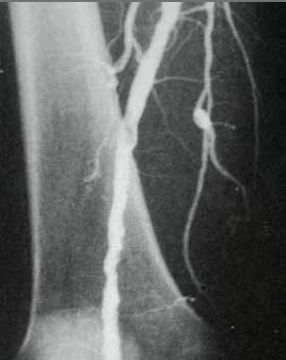

Verschluss der Oberschenkelarterie

... nach Wiedereröffnung (Dilatation)